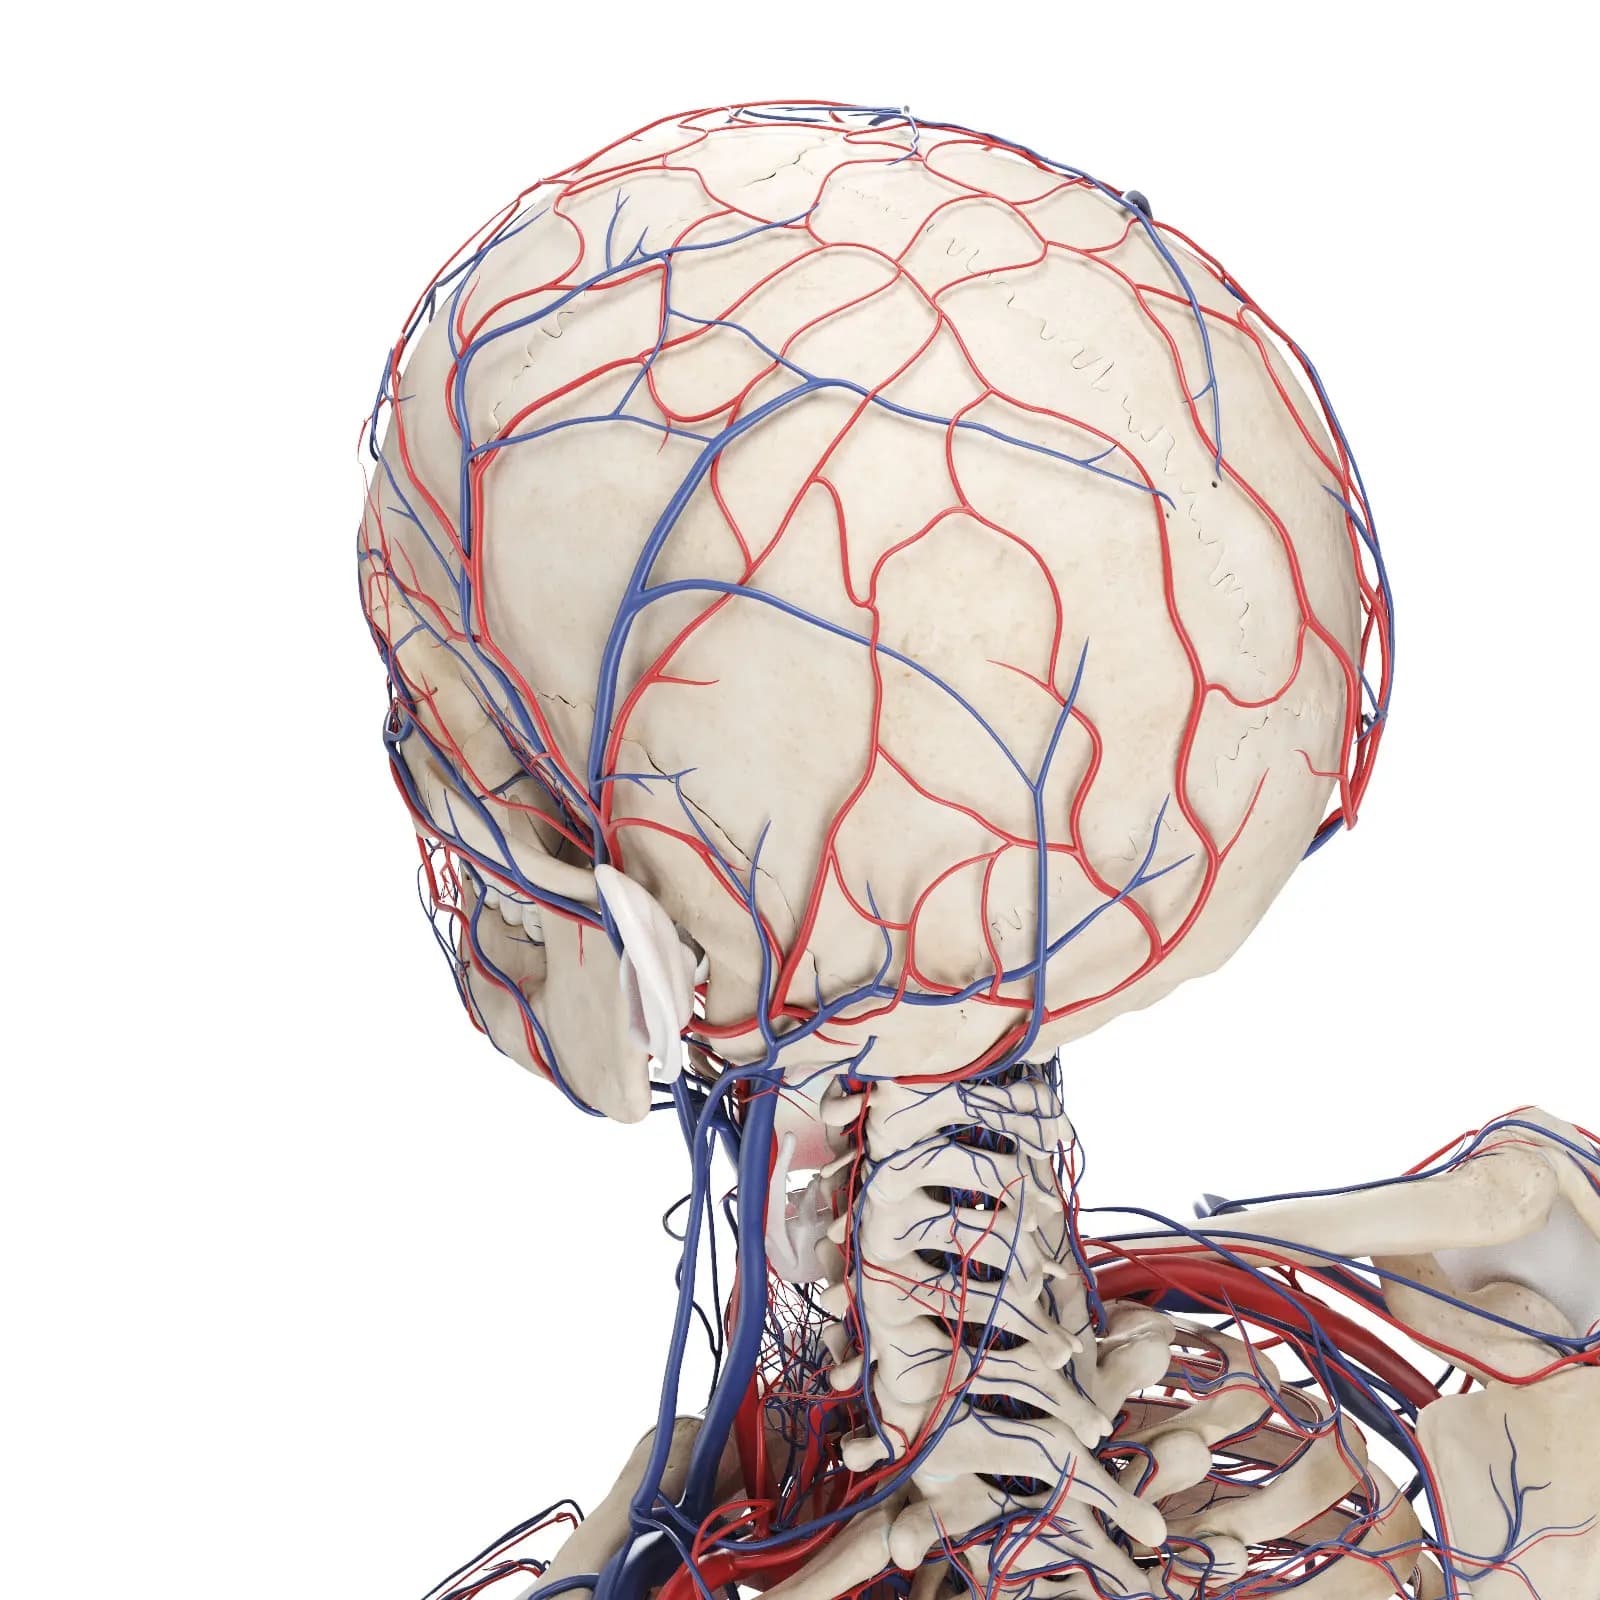

3d Rendered Medical Illustration Of The Vascular System Of The Head